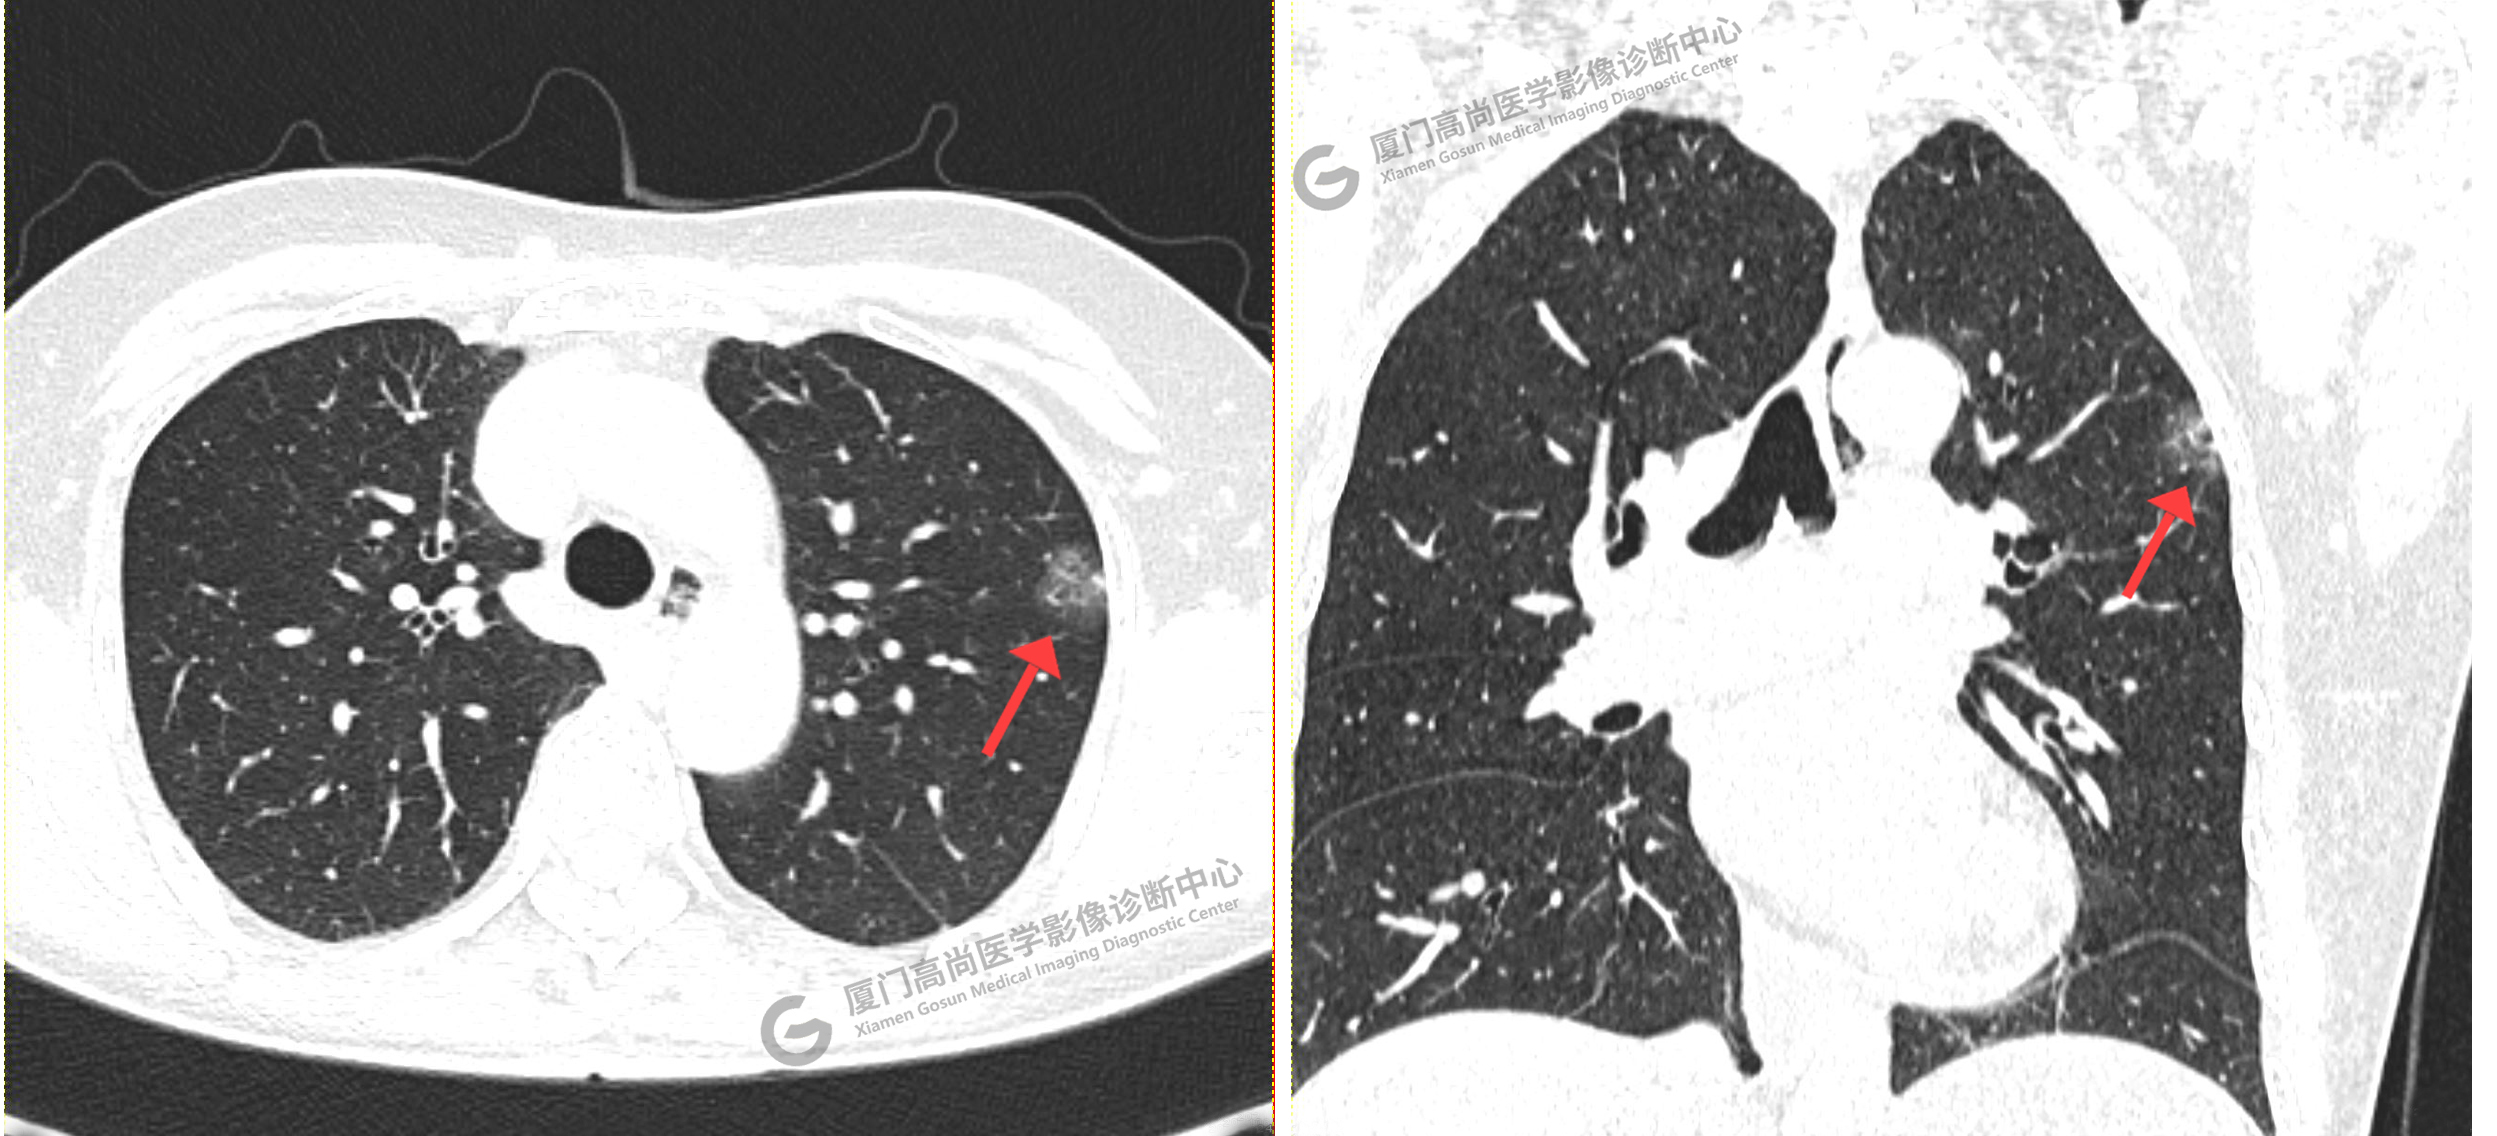

靶掃描影像圖

靶掃描示:右肺下葉實(shí)性結(jié)節(jié),考慮腫瘤性病變可能性大,建議PET-CT進(jìn)一步檢查。2、左肺上葉尖后段磨玻璃結(jié)節(jié)及右肺上葉淡薄小片絮影,建議短期隨診復(fù)查。

PET/CT影像圖

圖1

圖2

PET/CT示:右肺下葉結(jié)節(jié),代謝增高,考慮為周圍型肺癌,建議穿刺活檢。

病理證實(shí)是肺腺癌。